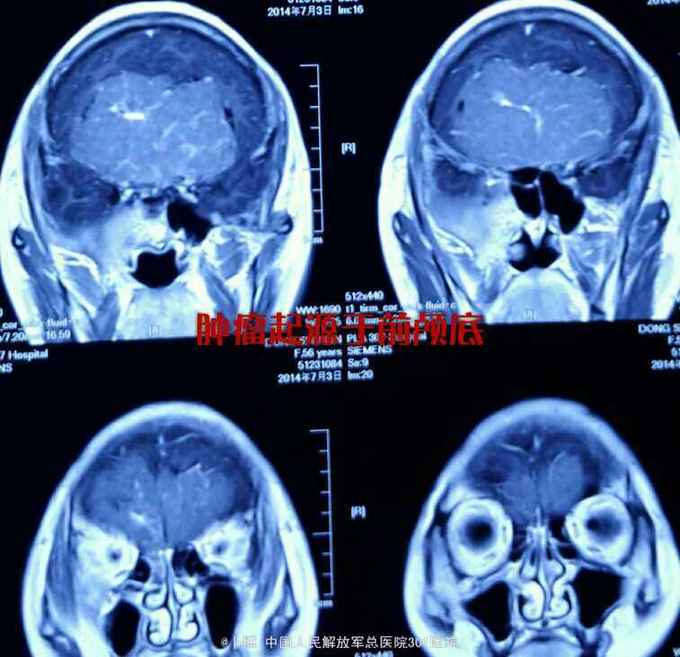

前颅窝底占位:脑膜瘤

脑膜瘤

头痛伴记忆力下降8个月。家属发现患者反应迟钝,记忆力下降。对人淡漠。

神清语利。定向力正常。计算力下降。双侧嗅觉丧失。视力下降,双侧0.5。眼底视乳头边界不清。眼球各方运动正常。余神经系统阴性。

前颅窝底占位:脑膜瘤。 手术入路:冠状切口,双侧额下入路肿瘤切除。